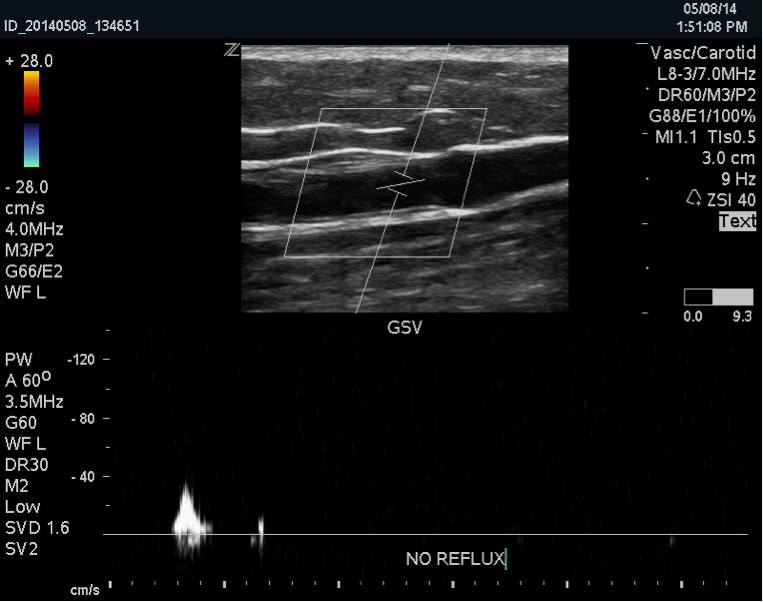

The Great Saphenous Vein is a vein of the superficial venous system that drains blood from the skin and tissues into the deep system. It is most commonly the root of the problem in people with varicose veins. When the great saphenous vein is dysfunctional, removing it is the first step of vein treatment.

A great saphenous vein that needs treatment is not functioning properly. When a vein is diseased, the walls become weak and the vessel can dilate or grow triple its’ normal size. This is not the type of vessel that would be ideal to place in a diseased heart. While the saphenous vein is a common vein that is harvested for bypass grafts, there are other options such as the internal thoracic artery in the chest and the radial artery which is in the arm. With these options, an artery replaces an artery and the removal of the valves inside the veins is not necessary. It is important for the entire circulatory system to be functioning properly, together.